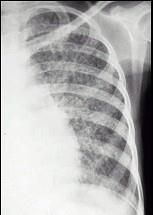

问题 女性,20岁,高热20天,伴乏力、盗汗、食欲减退及干咳。胸片见图。最可能的诊断是 ( )

选项 A.肺结核球 B.急性血行播散型肺结核 C.肺癌 D.肺脓肿 E.支气管扩张

答案 B